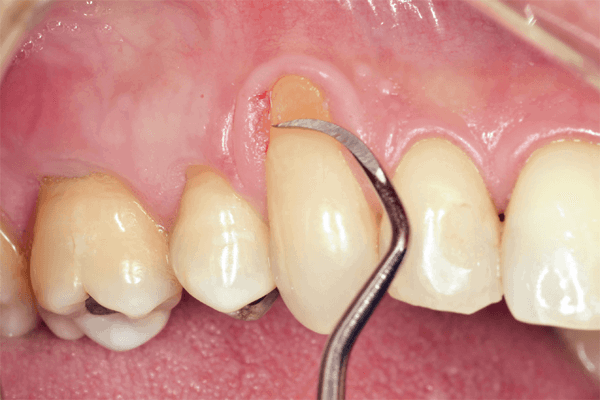

Para isto, existem diversos tratamentos, sendo as cirurgias de enxerto para recobrimento radicular as mais utilizadas.

A cobertura total das raízes por tecidos gengivais espessos e saudáveis é indispensável para eliminar esses sintomas severos. No entanto, é de grande importância o conhecimento de suas técnicas, indicações e contraindicações, a partir das considerações anatômicas de cada caso.